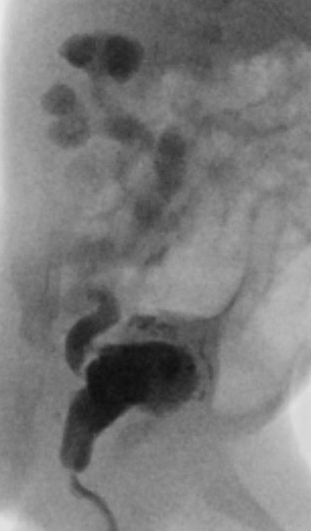

Normale plasbuis voorbij de kleppen

Plaats van de urethrakleppen

Verwijd eerste deel van de plasbuis tot aan de kleppen

Kleine, kramperige blaas met kartelige contour veroorzaakt door uitstulpingen van de blaaswand (divertikels)

Terugstroom van urine tot in de nier (vesico-ureterale reflux) en verwijde urineleider

Plasfoto met contrastmiddel (mictie cystogram)